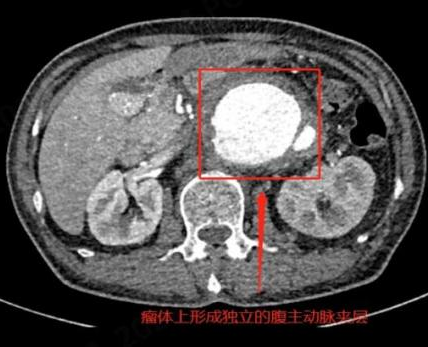

CT检查(计算机断层扫描)

CT利用X射线束对人体进行多层扫描,通过计算机重建出三维图像,提供更详细的解剖信息。

1.高分辨率三维图像:可以清晰地显示器官、血管、骨骼的细节。

●肿瘤诊断:如肺癌、肝癌、脑瘤等的早期发现和分期。

●腹部疾病:如肝胆胰脾肾等器官的病变。

●精准诊断:CT能够提供更详细的影像信息,帮助医生明确病变的性质、范围和严重程度。

●治疗指导:在手术前或放疗前,CT可以为医生提供精确的解剖信息,辅助制定治疗方案。